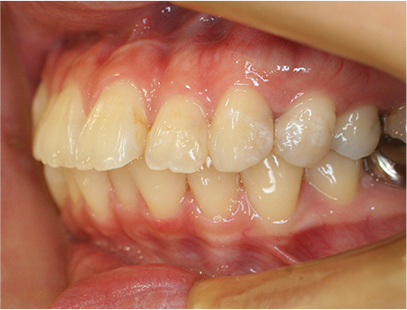

治療後

• 矯正治療後の横顔

• 正面

• 左側

• 右側

治療前の写真と比べると上下の前歯は後方に下がりました。

そのために、鼻の下の膨らみもすっきりして、下唇も薄くなることができました。

治療期間は2年と6か月を必要としました。